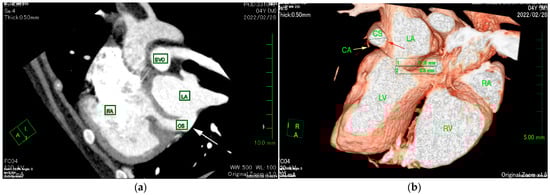

The ECG-gated CT showed communication between the LA and RA via the CS (Figure 2a). An enlargement of the CS, where the coronary artery measured 0.8 mm in diameter, whereas the CS measured 11.6 mm, was observed (Figure 2b). The CS drained normally into the RA; however, an ostium to the LA was seen, leading to the diagnosis of UCSS (Figure 3a). Under general anesthesia, TEE was also conducted using LISSENDO 880LE (Fujifilm Ltd., Tokyo, Japan) equipped with the 8–2 MHz phase array transesophageal probe (Fujifilm Ltd., Tokyo, Japan). With TEE, it was possible to identify the shunt as an abnormally large CS running along the cardiac wall (Figure 4).

When diagnosing UCSS, using just TTE may leave a risk of misdiagnosis [16]. In our case, the CS volume was overloaded. Considering that the mean diameter of the CS ostium in dogs is 5.5 ± 1.3 mm, the coronary sinus had become severely enlarged [17]. ECG-gated CT images showed that the diameter of the CS was 14.5 times larger than that of the coronary artery (Figure 2b). The largeness of the CS led to its appearance during the TTE as an irregular blood flow communicating between the LA to the RA, thus supporting the initial misdiagnosis of ASD. It is important to consider the possibility of extracardiac blood flow when no intracardiac defect is identifiable.

Figure 2. (a) ECG-gated CT multiplanar reconstruction (left oblique sagittal view) demonstrating the irregular communication between the RA and LA (arrow) that is formed by the unroofed CS. The opening in the CS allows blood flow from the RA to the LA. (b) ECG-gated CT volume rendering (sagittal slice, left lateral view, observed from the right) showing the markedly enlarged CS (red arrow) compared to the CA (yellow arrow). The CS measures 11.6 mm in diameter and is abnormally large compared to the CA, measuring 0.8 mm. CS, coronary sinus; CA, coronary artery LA, left atrium; LV, left ventricle; RA, right atrium; RV, right ventricle; SVC, superior vena cava.